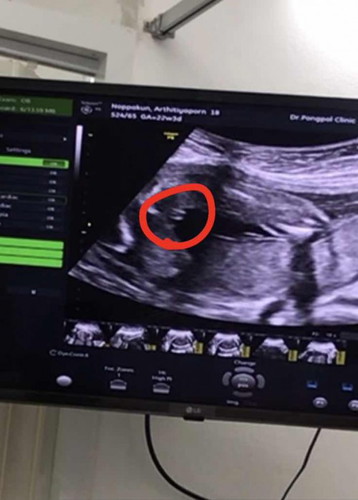

22w3d เพศชายหญิง

แม่ๆช่วยดูหน่อยจ้าแบบนี้ผู้หญิงหรือผู้ชาย👶🏻

ผู้หญิงจ้า

ผู้หญิง